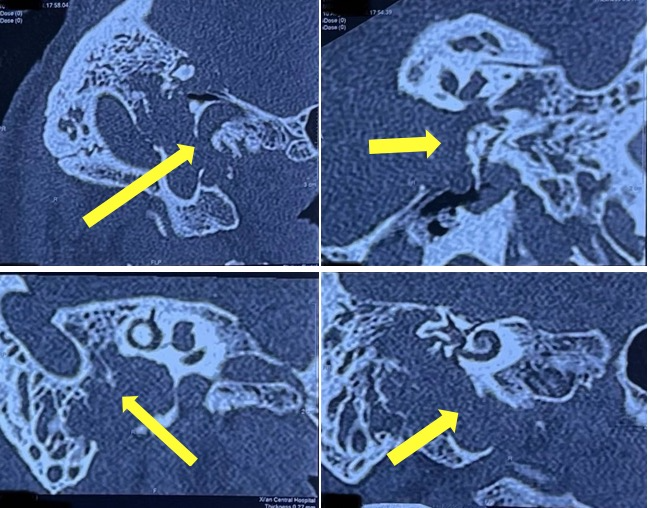

收住我科后,患者术前行面神经曲面三维重建显示右侧面神经膝状神经节段、鼓室段、乳突段骨质明显破坏。肿瘤向外累及中耳腔及外耳道,上方硬脑膜骨板、下方大血管及神经骨管均已被肿瘤侵蚀破坏(图1)。外耳道肿物进一步活检确诊为面神经鞘膜瘤(图2)。因肿瘤范围大,故手术难度高,术后脑脊液漏、大出血及感染等并发症发生率极高。且此类肿瘤在全国领先手术科室中术后均会出现单侧面瘫加重或全瘫,若切除肿瘤后不进行神经移植,则患者会永久性面瘫,影响美观。

图1 面神经三维重建CT,黄色箭头显示肿瘤侵及范围大